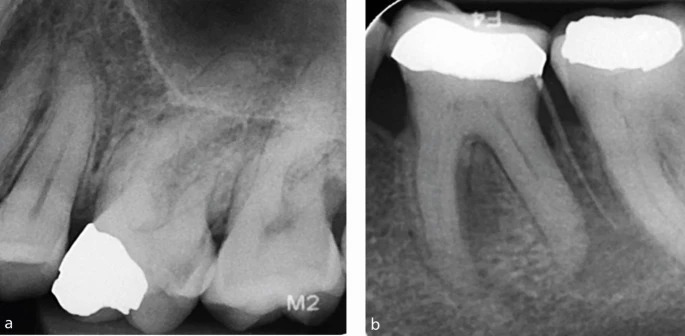

a) Зуб 26, требующий эндодонтического лечения, имеет значительно редуцированную пульповую камеру, что указывает на высокую сложность случая.

b) Зуб 36 также демонстрирует уменьшенный объём пульповой камеры, что повышает уровень сложности. Обратите внимание на гуттаперчевый штифт, показывающий место выхода свищевого хода. Сокращённый размер пульповых камер увеличивает риск ятрогенных повреждений, включая возможность перфорации.

a, b) Прицельные рентгенограммы зубов 36 и 46, оба из которых требуют эндодонтического лечения. В обоих случаях видны крупные, чётко выраженные пульповые камеры, что снижает сложность формирования полости доступа, поскольку камера и устья каналов легко определяются визуально.